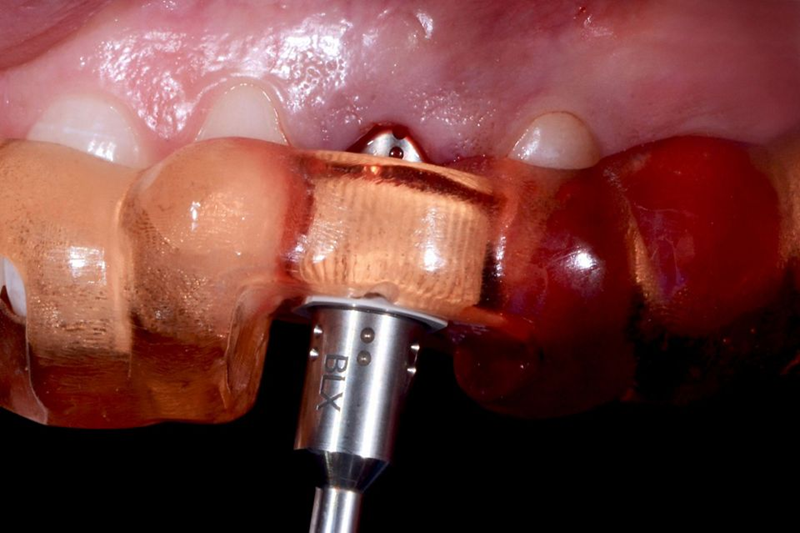

根据 CoDiagnostiX® 规划期间所做的选择,选择并放置了直径 4.5mm、长度 8mm 的 BLX®(图 35 - 36)。

Fig. 35: In accordance with the choice done during coDiagnostiX® planning, a BLX with 4.5 mm diameter...

Fig. 36: A detail of the pickup of the implant: the pin placed in the apical part of the implant was gently...

种植体在准备好的骨位点上以完美的引导接合到套管中(图 37),专用的 BLX® 转移件将种植体驱动到正确的位置(图 38)。种植体植入和移除导板后的咬合视图显示了最佳的 3D 种植体位置(图 39)。

Fig. 37: The implant ready to be engaged into the sleeve for the perfect guidance in the prepared bone site.

Fig. 38: The dedicated BLX transfer piece drove the implant in the correct...

Fig. 39: Occlusal view after the implant placement and the removal of the...

尽管可用骨量减少,但种植体稳定性仍可能达到 35n/cm 的扭矩值,这使得可以立即放置假体(图 40)。将直径为 3.8 毫米、牙龈高度为 1.5 毫米的定制临时基台用螺钉固定在种植体顶部(图 41)。然后,用棉球保护临时基台的烟囱,以避免在后续步骤中堵塞螺钉的入口。然后将临时牙冠放入透明面罩内;在用树脂填充牙冠后,通过透明面罩将其固定到位,以便与临时基台连接。树脂聚合后,拧下临时牙冠(图 42),牙冠和基台之间的空间填充树脂,然后进行调整,直到获得适当的紧急轮廓(图 43)。